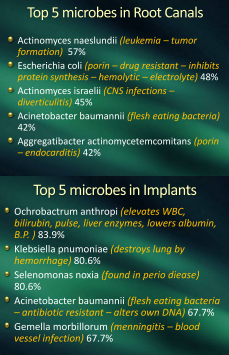

I dream that dentistry will finally discover

hundreds of microbes living under cover

Heart disease and even cancer

are not a normal healthy answer

Root canals have no MHC

so they become your enemy

I dream we’ll use our DNA

to chase the anaerobes away

They also provide a hiding place

for Lyme’s Borrelia to embrace

Why not pull teeth and place implants

certainly this is the circumstance

They take little care to keep them clean

and surgery is not that extreme

Root canals certainly produce their share

of bacteria that tend to scare . .

Pathologists looking for disease

but implants tend to make them freeze

Implants by far collect the worst

they are the ones that call the hearse

Have a bridge or would you rather

have an implant and become a cadaver